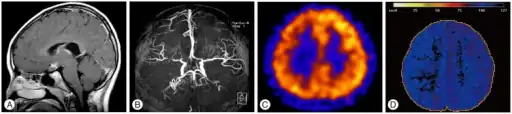

![]() | |

| T1-weighted MR image of moyamoya disease. Flow void in the basal ganglia is indicated by the arrow. | |

Moyamoya disease is a disease in which certain arteries in the brain are constricted. Blood flow is blocked by constriction and blood clots (thrombosis).[1] A collateral circulation develops around the blocked vessels to compensate for the blockage, but the collateral vessels are small, weak, and prone to bleeding, aneurysm and thrombosis. On conventional angiography, these collateral vessels have the appearance of a "puff of smoke" (described as "もやもや (moyamoya)" in Japanese).[1]

Magnetic resonance angiography (MRA) is also useful in diagnosing the disease with good correlation with Suzuki's grading system.[14]

Often nuclear medicine studies such as SPECT (single photon emission computerized tomography) are used to demonstrate the decreased blood and oxygen supply to areas of the brain involved with moyamoya disease. Conventional angiography provides the conclusive diagnosis of moyamoya disease in most cases and should be performed before any surgical considerations.